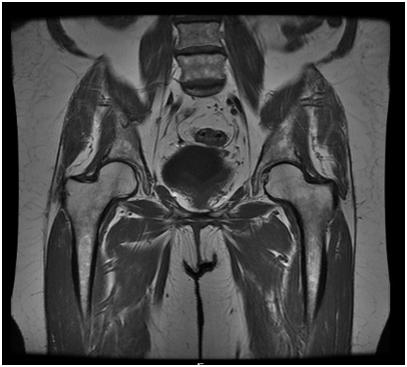

MRI of the pelvisPelvis MRI